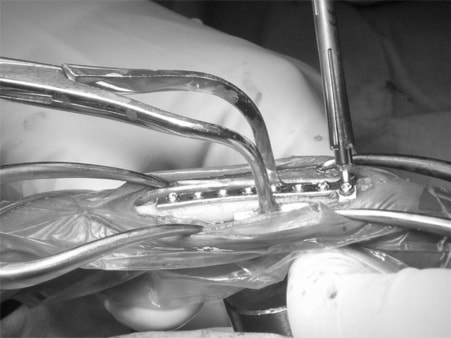

脊髄の減圧、脊柱管の再構築・安定化を目的に、片側椎弓切除術およびMatrixMANDIBLE Plateによる椎体固定を実施しました。

隣接椎体を架橋するようにプレートを設置しました。

術後レントゲン写真